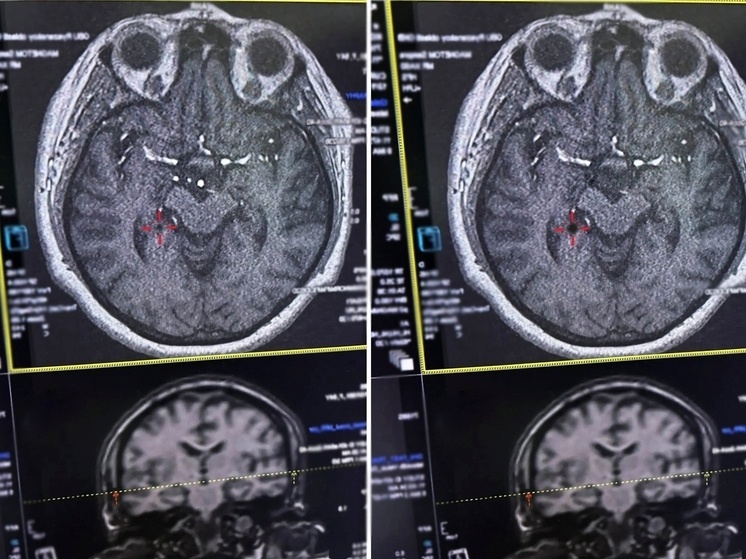

Во время госпитализации у пострадавшей была парализована правая часть тела, а также наблюдалась выраженная головная боль. Как уточнили в Министерстве здравоохранения, бригада врачей оперативно начала лечение в первые четыре с половиной часа после приступа, что критически важно при инсульте.

Медикам удалось провести тромболизис — процедуру по растворению тромба с помощью специальных препаратов. Именно своевременное вмешательство помогло стабилизировать состояние женщины.